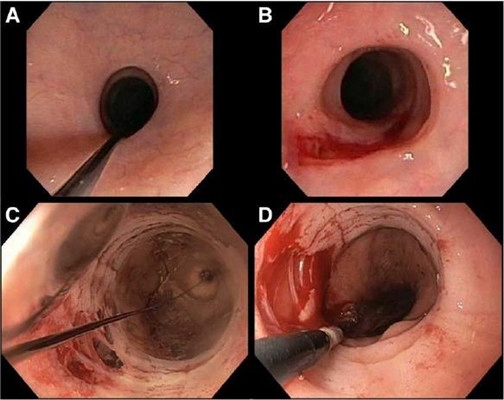

食道炎圖片